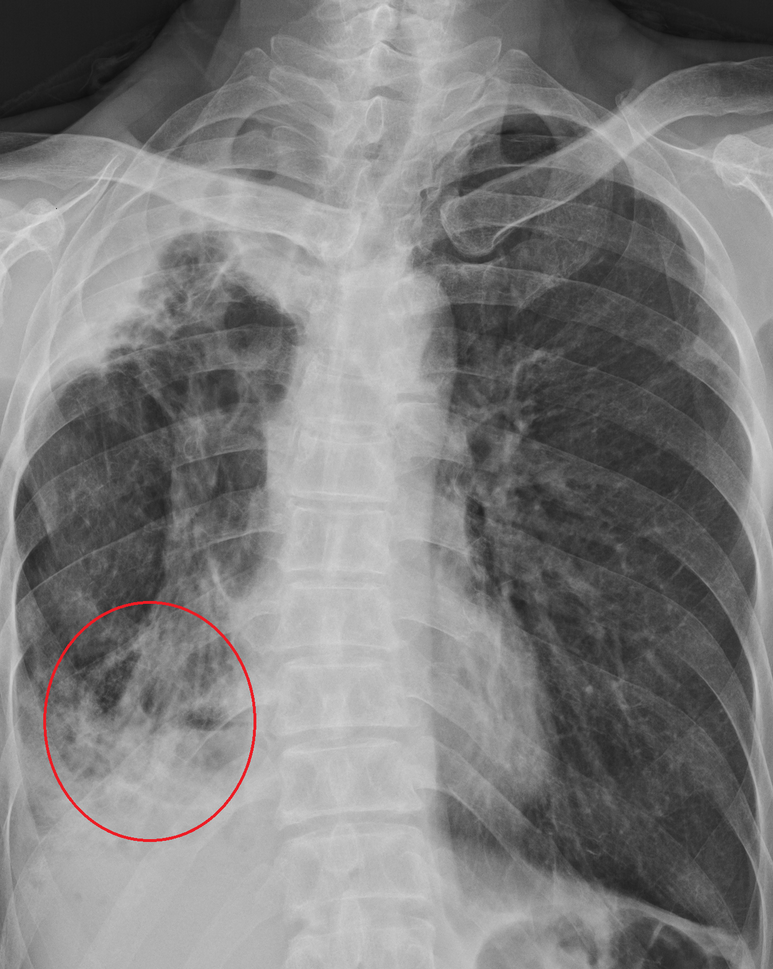

x-ray는 아래와 같다. 청진상 폐음은 특이사항 없음

(영상의학과 판독은 오른족 아래 폐렴이나 임상적으로 감염의 증상은 없었다. 과거력과 같이 하여 다음에 가래검사 평가하기로 함)

x-ray 추적; 영상의학과 판독은 "변화는 없으며 폐렴"

임상적으로 폐렴 소견은 아니며, 가래 검사에서 결핵균 없음 및 가래 중간 배양 검사에서 자라는 항산균, 결핵균은 보고되지 않았다.

최근가지 흡연력이 있으며 단순 x-ray로 평가에는 한계가 있으므로 폐 CT 받도록 안내하였으며 지인이 있는 대학병원에서 촬영하기로 계획하였다.